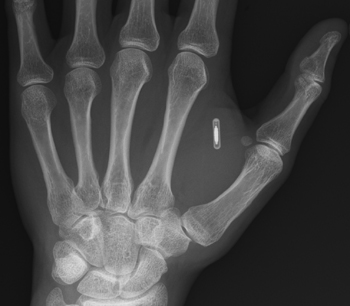

Εμφυτεύοντας στο χέρι του ένα μικροτσίπ RFΙD το οποίο σε ρόλο «κλειδιού» τού παρέχει πρόσβαση σε συγκεκριμένους χώρους και εργαστήρια εντός των κτιριακών εγκαταστάσεων του πανεπιστημίου, ο ερευνητής μελέτησε τα κενά ασφαλείας της φουτουριστικής εφαρμογής, καθώς μέσω του ειδικού συστήματος ανάγνωσης κατάφερε να μολύνει το μικροτσίπ με έναν ηλεκτρονικό ιό.

Η πληροφορία που κουβαλούν τα ανθρώπινα εμφυτεύσιμα μικροτσίπ RFΙD, όπως ξεκαθαρίζει ο δρ Γκάσον, είναι ένας 16ψήφιος κωδικός ο οποίος μεταδίδεται μόνο όταν «διαβαστεί» με τον «ειδικό αναγνώστη». Στην περίπτωση των ζώων, αυτός περιορίζεται σε 10 ψηφία.